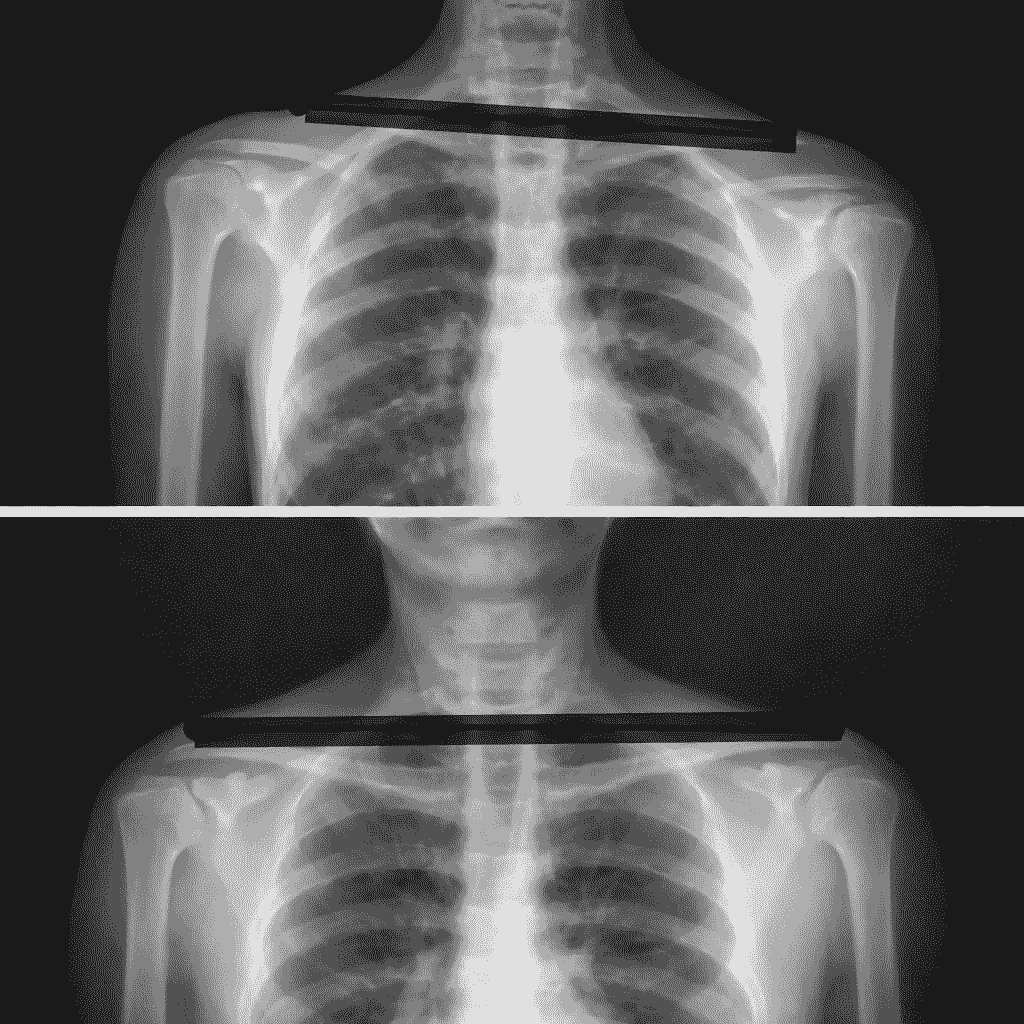

Shoulder asymmetry is not yet a true postural defect—it is rather a deviation / faulty posture. Lowering of one shoulder compared to the other may be linked to careless posture, incorrect habits, or spending too much time in a sitting position. The first symptom that should concern us is back pain and tension. Over time, joint cartilage degeneration may occur. A common cause is pelvic rotation.

The pelvis plays a key role in spinal alignment. Due to a long-lasting incorrect pelvic position, permanent changes may develop in the lumbar, thoracic, and cervical spine. As a result, irreversible damage to intervertebral discs, facet joints, or hip and knee joints may appear, causing pain.

The pelvis is also closely related to body symmetry. It carries the entire vertebral column and has a direct connection with the lower spine and lower limbs. Because of that, any movement of the pelvis results in changes in vertebral position and affects lower-limb movement.

Scientists analyzing biomechanical disorders have noticed that incorrect alignment between spinal sections may lead to pathological conditions. The pelvis is the foundation of the spine, and its correct positioning strongly affects the maintenance of normal spinal curves. What happens in the pelvic girdle can also influence the cervical spine. Therefore, it is important to assess every spinal section, even if the patient complains.

In one study, the cause of vertebral fixation in over 80% of 105 patients was uneven weight bearing between the lower limbs exceeding 5 kg. After manipulation of fixed vertebrae, more than 70% of them were able to distribute weight equally while standing on two scales. Recurrence of the results after this treatment was found in 85% of patients. Better outcomes were observed when the fixed vertebrae were located in the upper cervical spine. If, during the two-scale standing test, a large difference in weight distribution between legs is detected, the craniocervical junction should be examined, including C2–C3. A difference of less than 2 kg does not seem significant.

According to Karl Lewit, a weight-bearing difference greater than 5 kg in adults and 3 kg in children should be considered pathological. However, based on my many years of clinical experience, I have concluded that even a difference exceeding 2 kg is already too large. With appropriate therapy, we are able to reduce this asymmetry to a minimum—around 2 kg, rather than 5 kg as Lewit originally suggested.